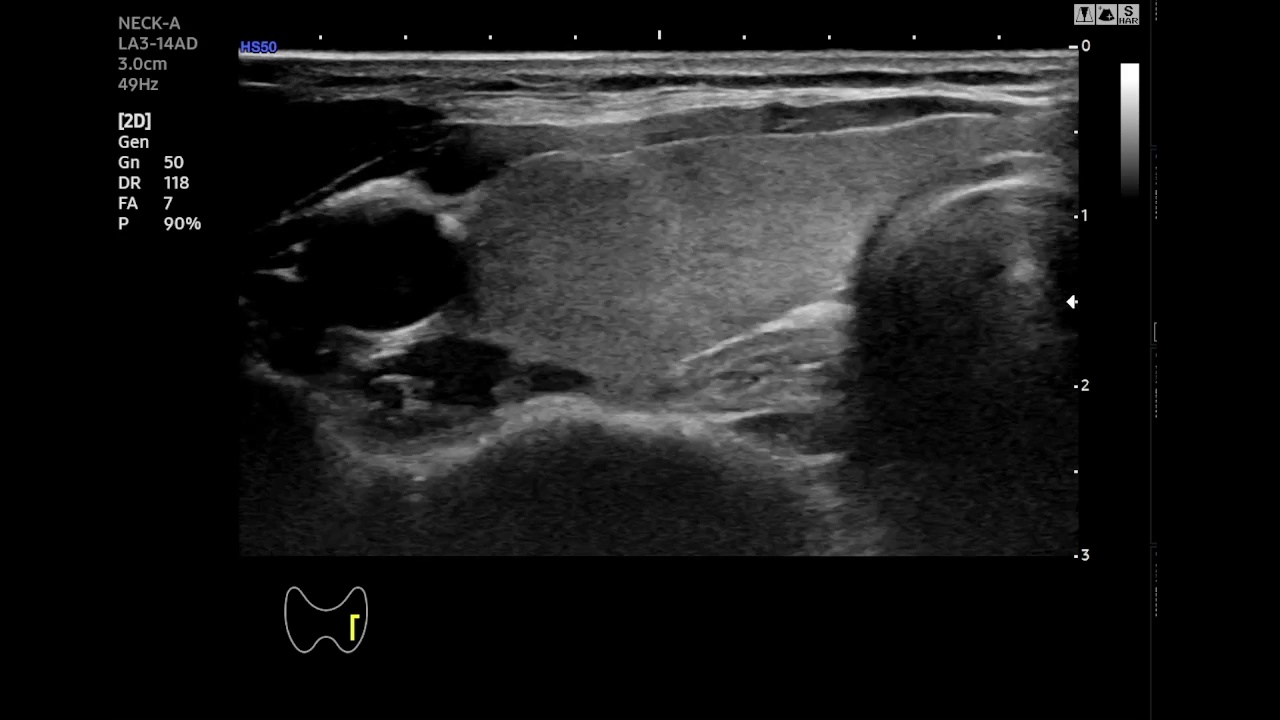

We curated a proprietary dataset comprising 13 B-mode ultrasound videos collected from 13 individual patients undergoing radiofrequency ablation (RFA) for papillary thyroid microcarcinoma (PTMC). The total duration of the dataset spans 124 minutes, with each video averaging approximately 10 minutes in length.

The ultrasound data were acquired using clinical-grade imaging systems commonly employed in thyroid diagnostics. Specifically, we utilized Philips Affiniti 70 and Samsung RS80A ultrasound systems operating in B-mode (brightness mode). The probes used were high-frequency transducers operating in the 15–18 MHz range, optimized for thyroid imaging. All images were captured at a spatial resolution of 786 × 531 pixels. Scan settings, including gain, depth, and focus, were manually adjusted for each patient based on anatomical characteristics.